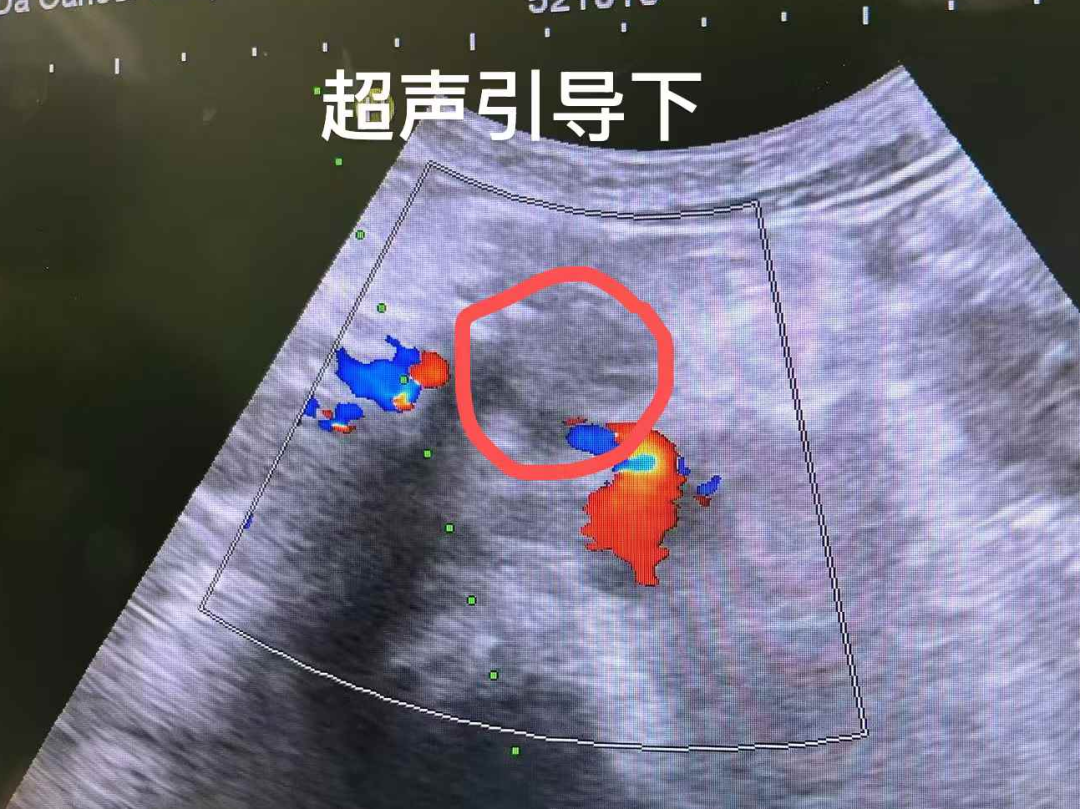

经过多学科会诊评估,医疗四科团队为她实施了胰腺肿瘤纳米刀消融术+腹腔神经丛阻滞术,术后结合免疫治疗,旨在控制肿瘤的同时缓解癌痛。

“纳米刀消融不到一小时就完成了。”莫林回忆道。这与她最初听说需要八小时的印象形成鲜明对比。即使在ICU观察的那一夜,医护人员温暖的陪伴也让她倍感安心。术后几天,奇迹开始显现,她重新找回人的本能:有了胃口,能够安睡,体重也开始回升。随后,莫林又接受了动脉灌注化疗术。